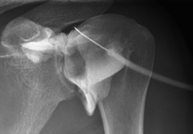

Técnica mediante la cual, utilizando rayos X, se obtienen imágenes del interior de las extremidades para su estudio, especialmente de los huesos. Indicaciones: traumatismo, infecciones articulares. - RX Artrografía

Procedimiento que permite, mediante el uso de rayos X, y tras inyectar un contraste en el interior de la articulación, detectar lesiones de determinadas articulaciones (cartílago, hueso, tendones, etc.) según la distribución del contraste. - RX Pelvis